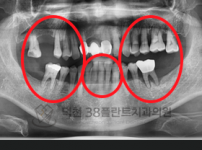

치료전후